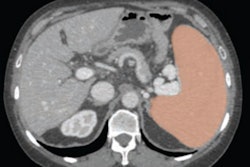

The study included 249 adult patients whose splenic length, width, and thickness were measured on CT. From these measurements, splenic volume and the relationship between the inferior spleen and surrounding organs, such as left lobe of liver and left kidney, were evaluated. Sixty-two patients (24.8%) patients had splenomegaly.

Dr. Alexandre S. Bezerra and colleagues used an established upper limit of normal for splenic volume (314.5 cm3), and derived a maximum spleen length of 9.76 cm and a maximum spleen width of 11 cm from the linear regression equation. Also, they determined that when the spleen reached or extended below the lower third of the left kidney, this was highly specific for splenomegaly despite a low sensitivity (sensitivity 20%, specificity 93%).

The study validated the use of a simple splenic length measurement for splenic CT volume. When splenic length exceeds 10 cm, a diagnosis of splenomegaly should be made. This clinically practical, accurate, simple measurement replaces multiple-measurement, time-consuming methods, and allows daily routine follow-up, the authors reported.